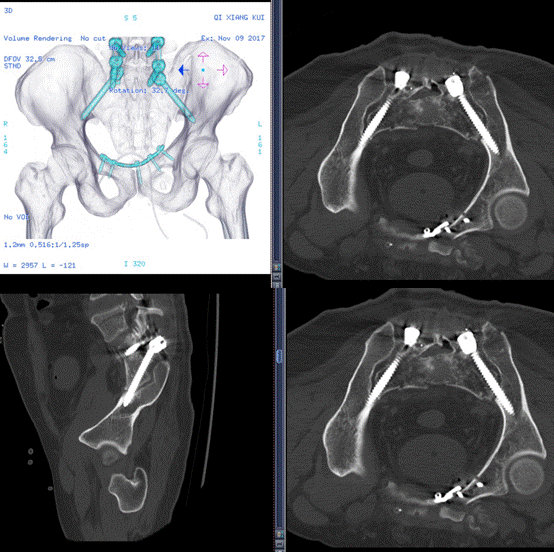

术后CT